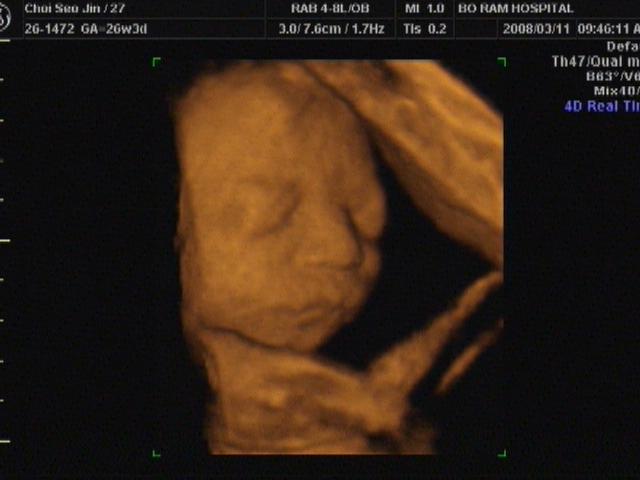

그리고 애기 입체 촘파 올려요~~ 태명은 양파깡.. 남자아이구요..

31주 4일에 2키로 나갔답니다.. 모든게 다 정상이구요.. 아주 잘 크고 있데요..